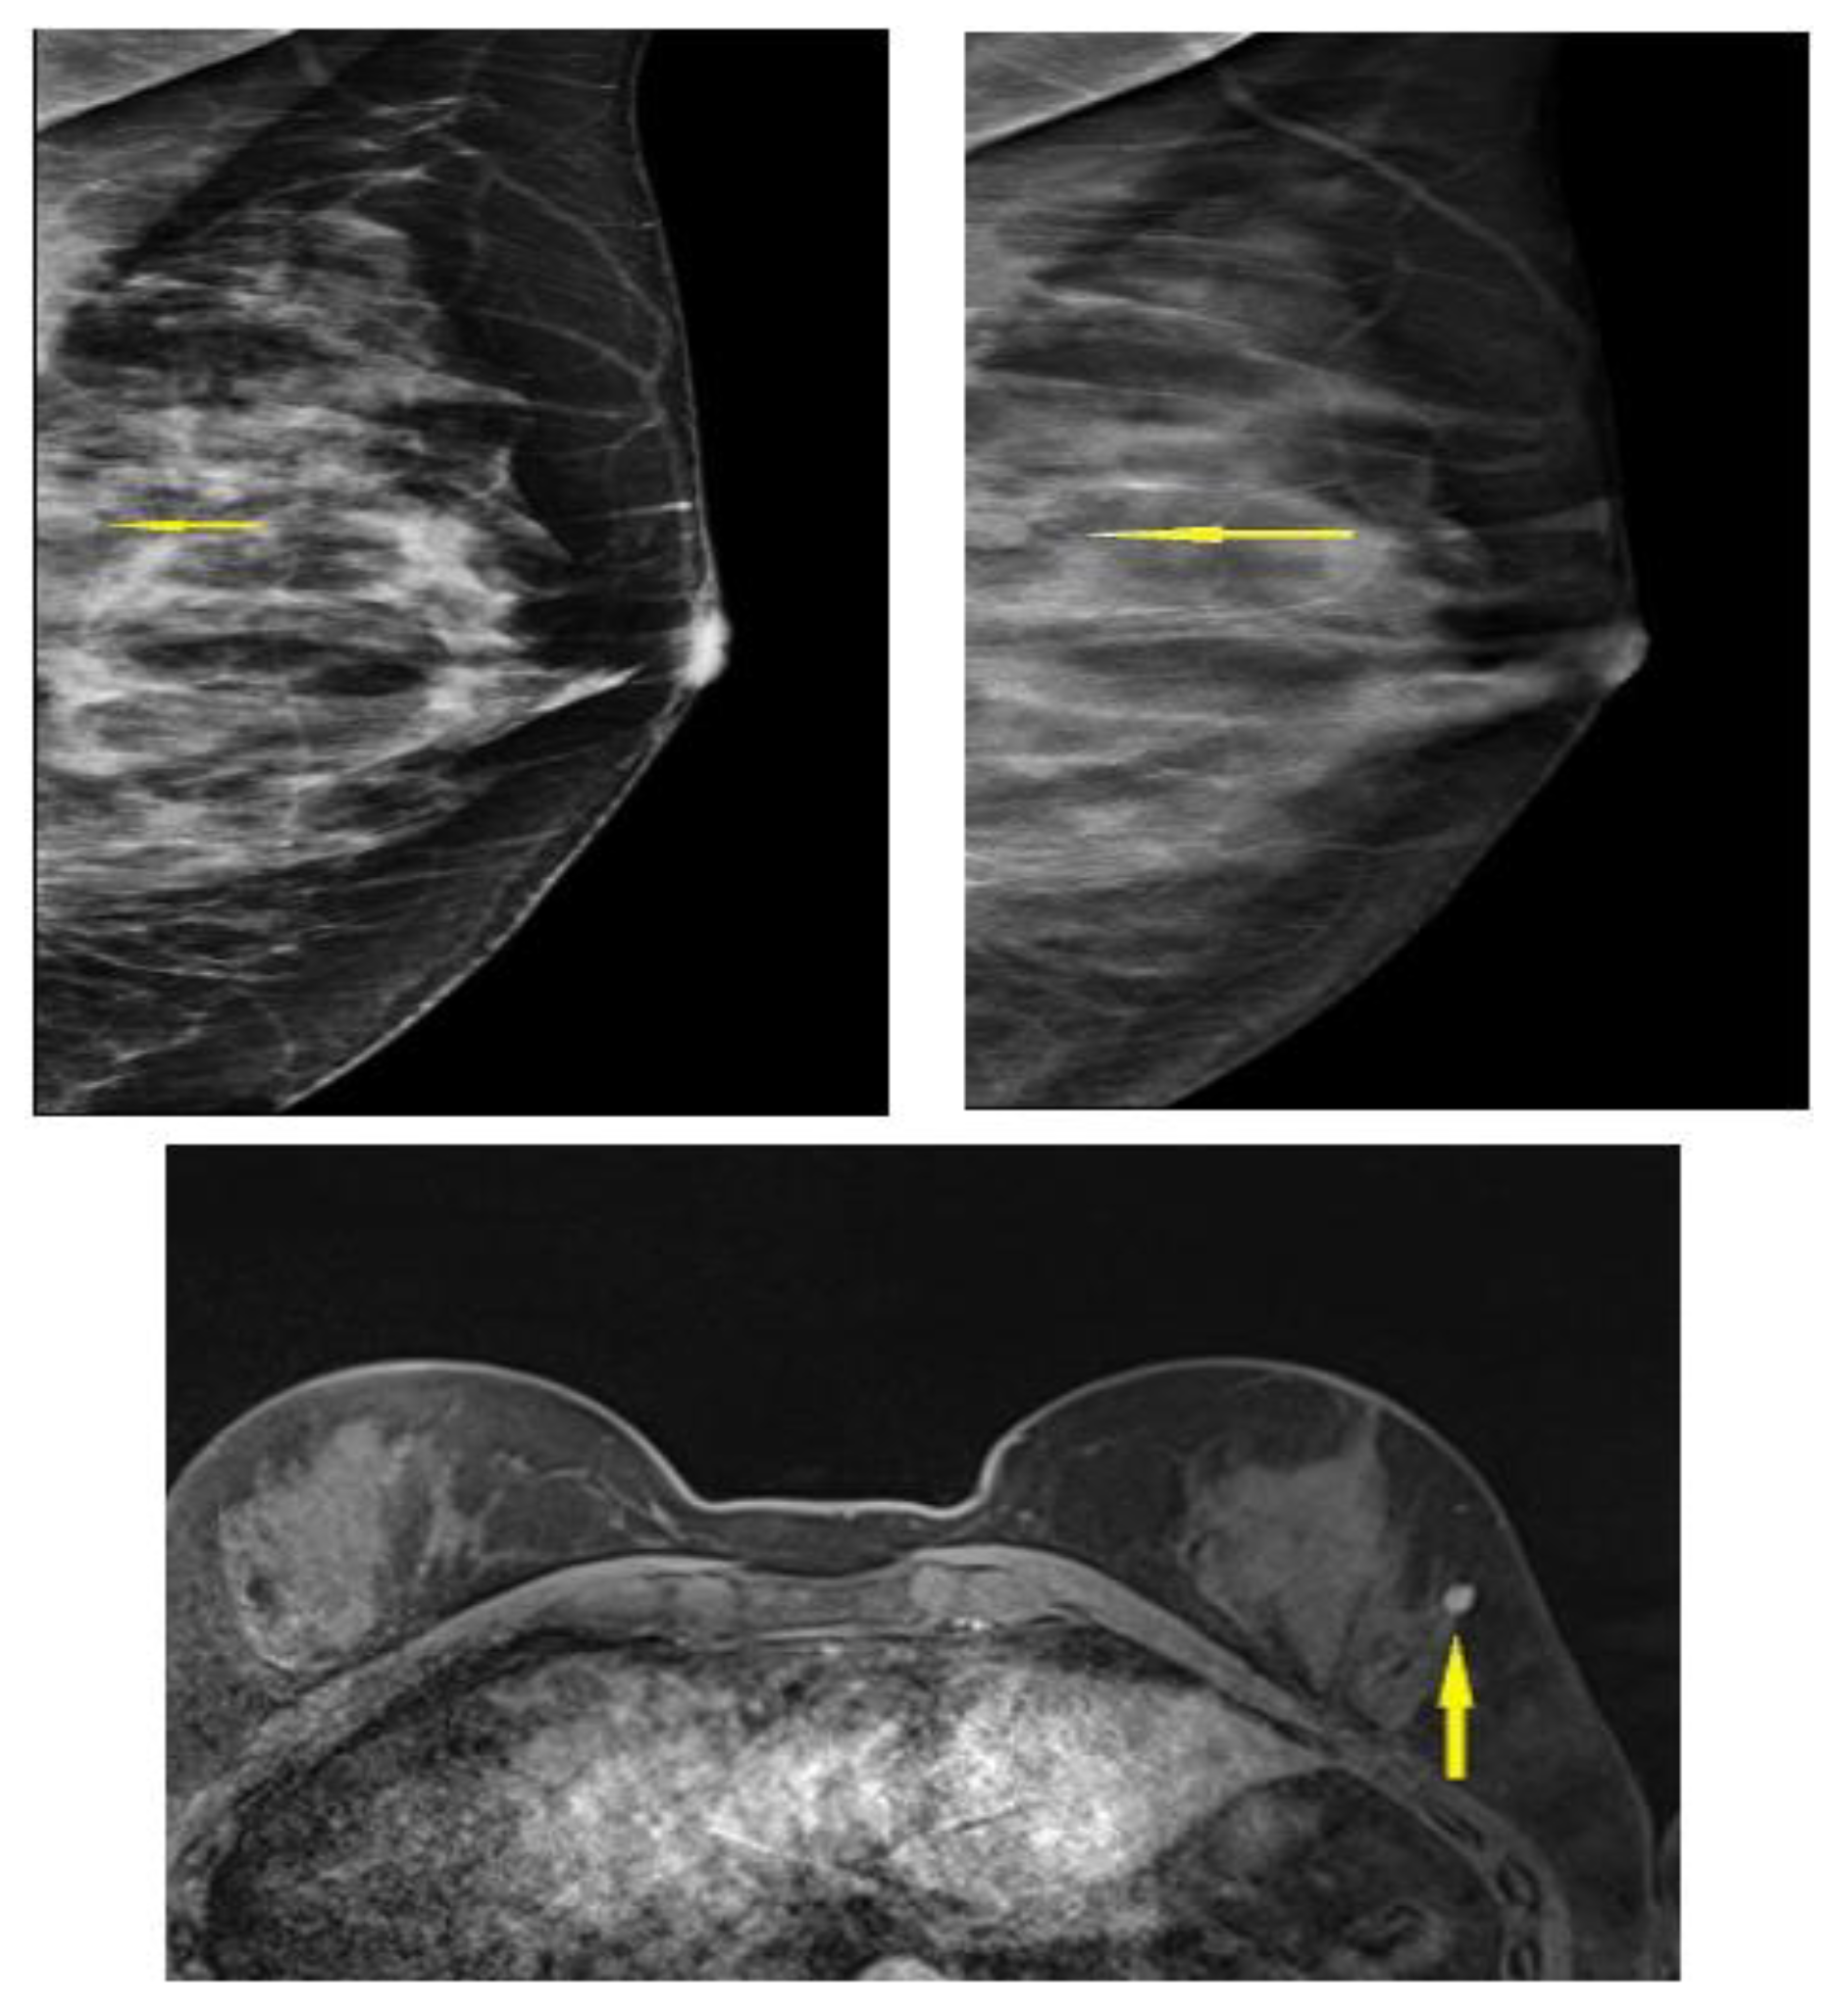

3.4. Selected Interesting Examples from Our Study